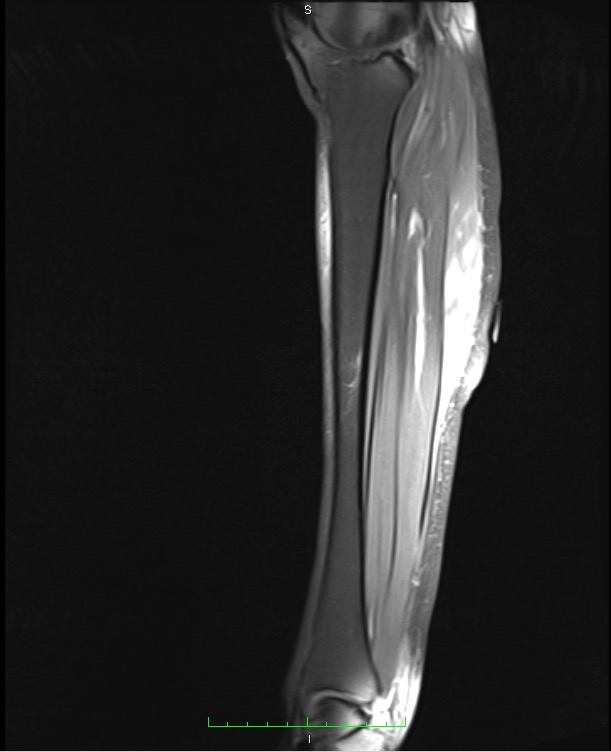

Findings of the initial workup by the primary care provider were negative for deep vein thrombosis on Doppler ultrasonography and negative for arterial insufficiency on ankle-brachial pressure index. Electromyography findings were negative for myopathic or neuropathic abnormalities. Magnetic resonance imaging (MRI) scans of the lower extremity showed hyperintensity on fat-suppressed T1-weighted images of the musculature with associated subcutaneous nodularity (Figures 1 and 2).

Figures 1 and 2. MRI scans of the right lower extremity showed nodularities and nonspecific inflammation within the leg muscles, particularly the tibialis anterior and gastrocnemius muscles.

As illustrated by this case, the diagnosis of muscle-limited vasculitis can be extremely challenging. MRI can aid in the diagnosis by showing increased signal intensity in the affected calf muscles and subcutaneous tissue on fat-suppressed images, which indicates edema from an inflammatory process.4-7 Moreover, MRI findings give clues as to which area of the muscle must be biopsied and also can guide response to therapy. All of the reviewed cases of muscle-limited vasculitis involve the lower extremities. Most often, the gastrocnemius and soleus muscles are involved.2,4-7 MRI comparison images in one case report have shown decreased signal intensity after treatment.4